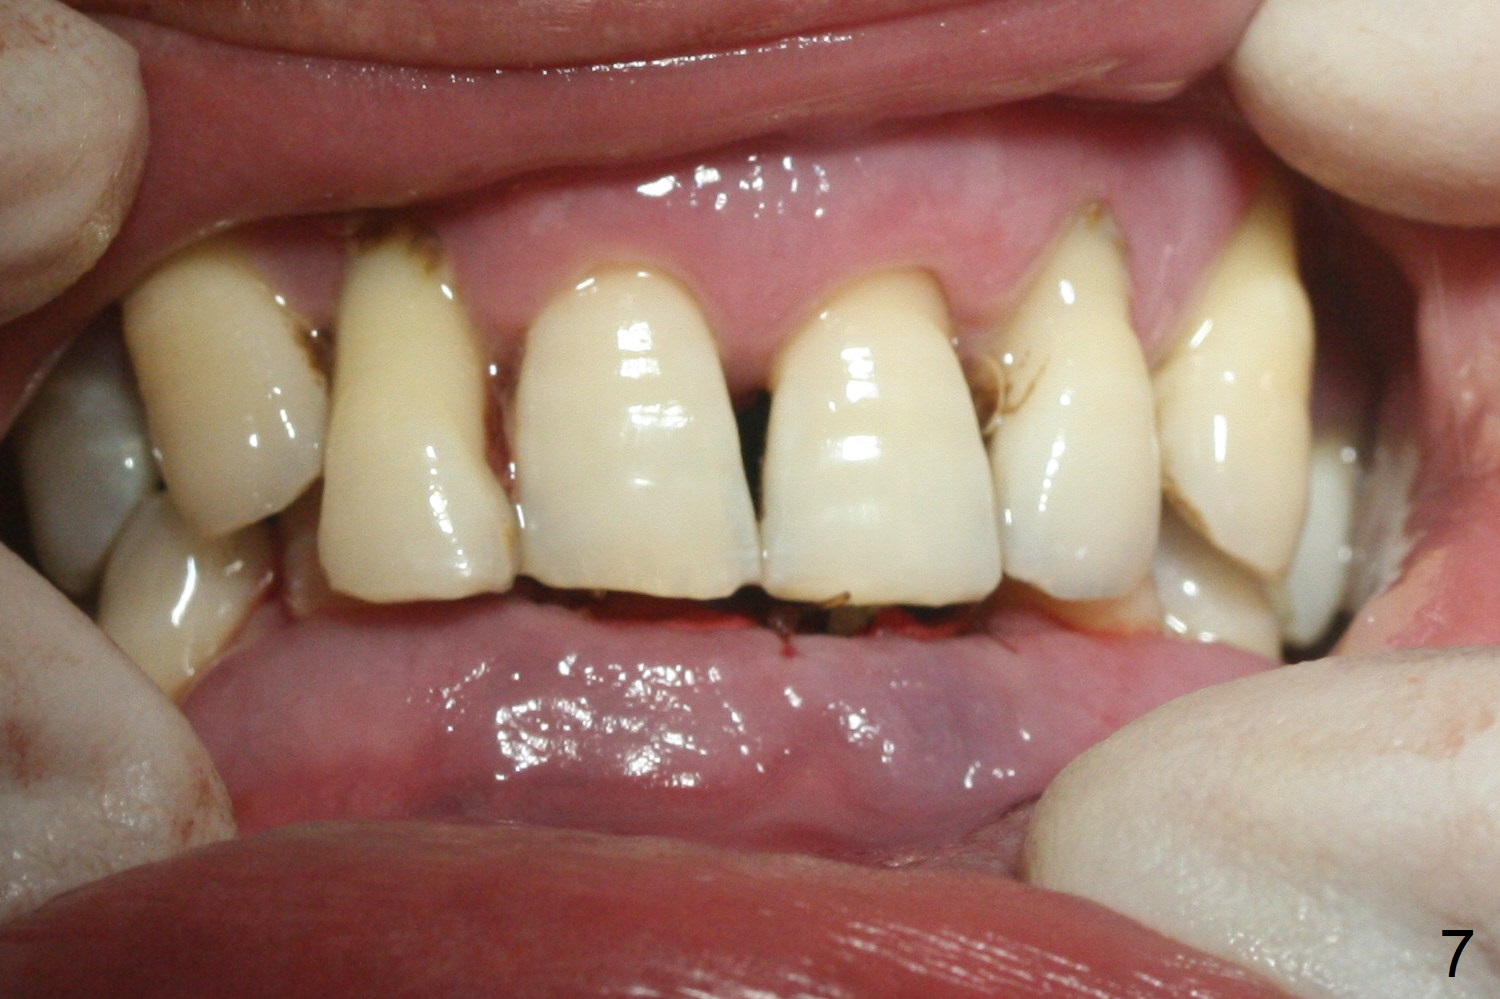

After extraction of 4 of the lower incisors, there are basically 2 sockets (#23/24 and 25/26), separated by the apparently midline bone (Fig.1 red line).  In spite of using Lindamann bur to move the 25/26 osteotomy mesially, a 3x14(2) mm dummy implant remains close to the tooth #27 (Fig.2).  The terminal branch of the Incisive Canal (<) is located between the lateral and central incisors.  A de novo osteotomy (Fig.3 (1.5 mm drill)) is made mesial to the original one (O).  While the 3x14(2) mm dummy implant is incompletely placed at #25/26, a 3x14(4) mm 1-piece one is placed at #23/24 (Fig.4).  Finally the same implant is placed at #25/26 with placement of mineralized cortical/cancellous bone (Fig.5 *).  When the large sockets are sutured, the supraerupted teeth #7-9 touch the lower gingiva (Fig.6).  The incisal edge is reduced for clearance (Fig.7).  Periodontal dressing is less likely to be dislodged with the incisal edge reduction (Fig.8,9).  A provisional FPD is fabricated 1 week postop.  Hard (Fig.10) and soft (Fig.11,12) tissues heal 5.5 months postop.  The patient returns for crown cementation 3 months post impression (9 months postop, Fig.13,14).